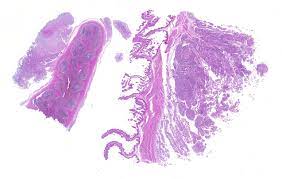

Conference 7 2017 Case 2 20171018

Conference 7 2017 Case 2 20171018 from www.askjpc.org